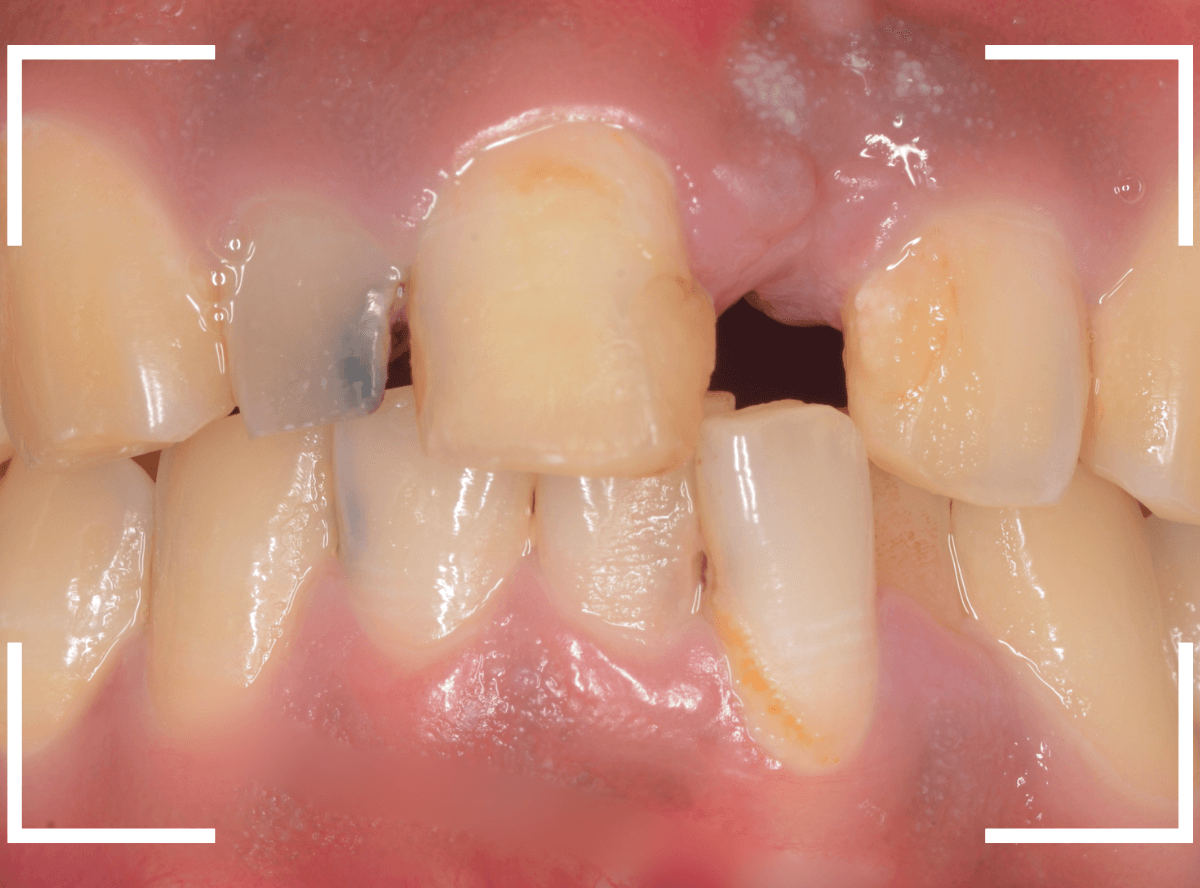

さし歯の中には大きなメタル・コアが入っています。。。

さし歯の周りの歯肉が若干黒ずんでるのも、これが原因でしょう。

せっかくさし歯をやり直すのであれば、このメタル・コアもやりなおしたいところです。

かなり怖かったですが、患者さんにも頑張っていただいて、さし歯を除去後、時間をかけて慎重にメタルコアを除去しました。

無事にメタルコアを除去できましたので、ファイバーコアに置き換えます。

歯肉の治療がひと段落したところで、ジルコニア・セラミックで再製しました。